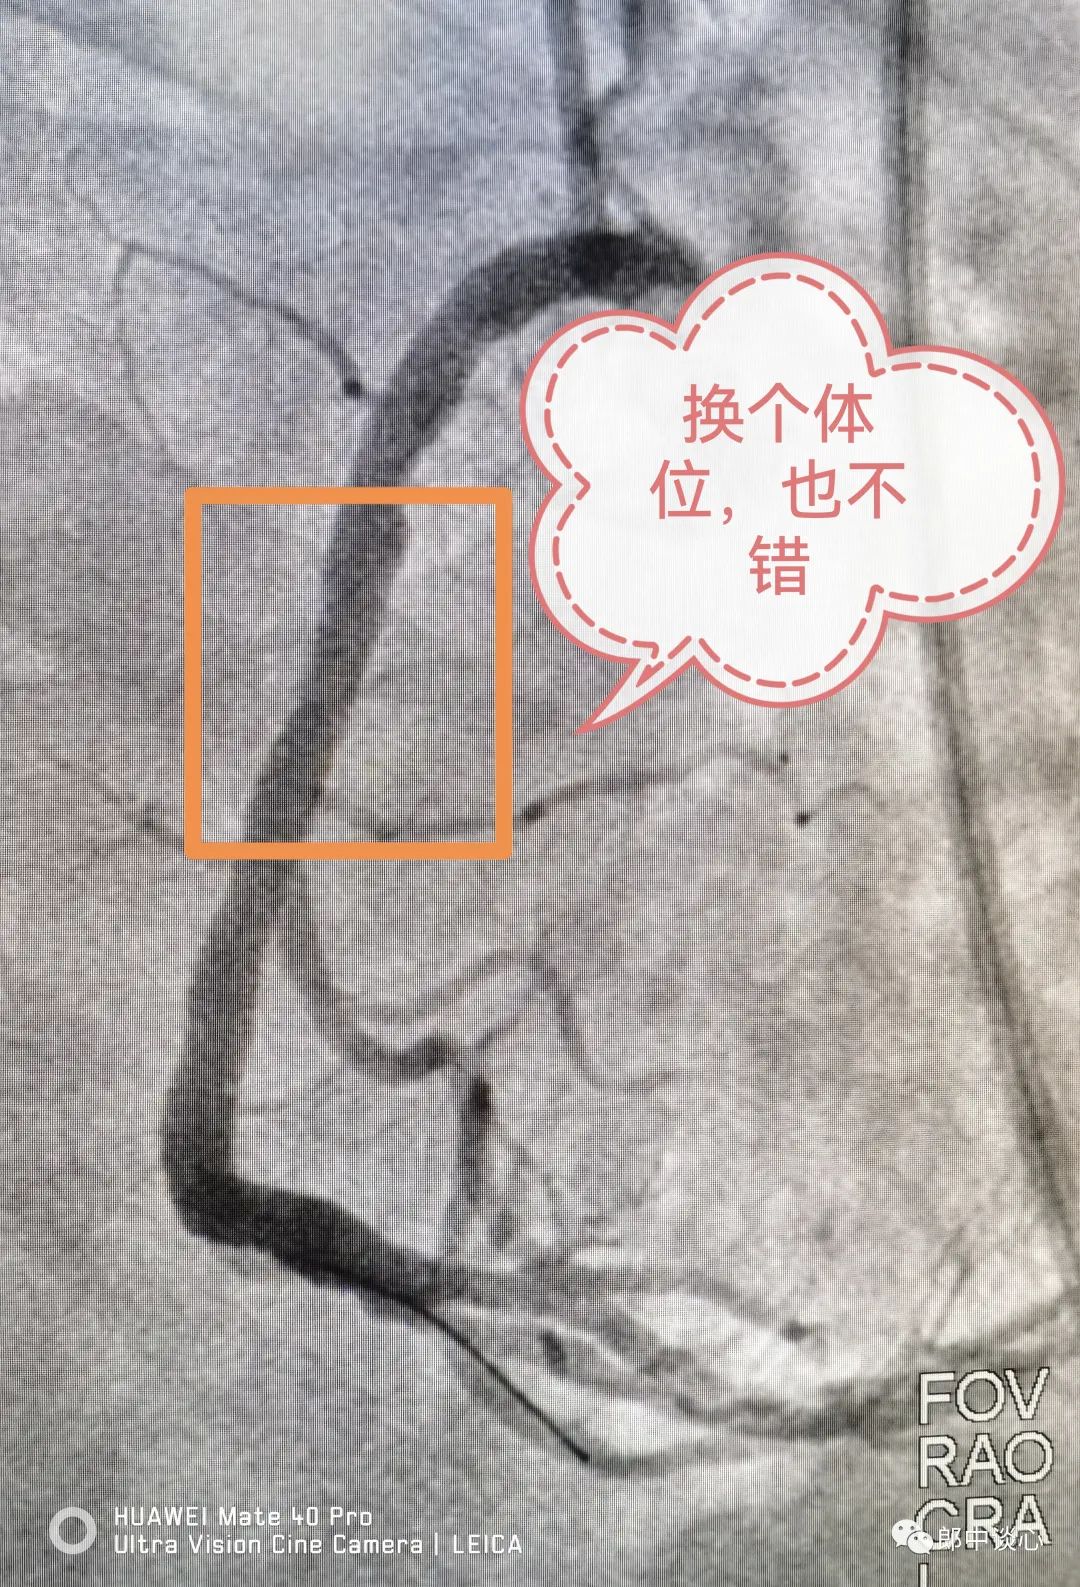

冠脉造影,果然前降支完全闭塞了!回旋支也是重度狭窄且是不稳定病变!(黄框内为病变段)